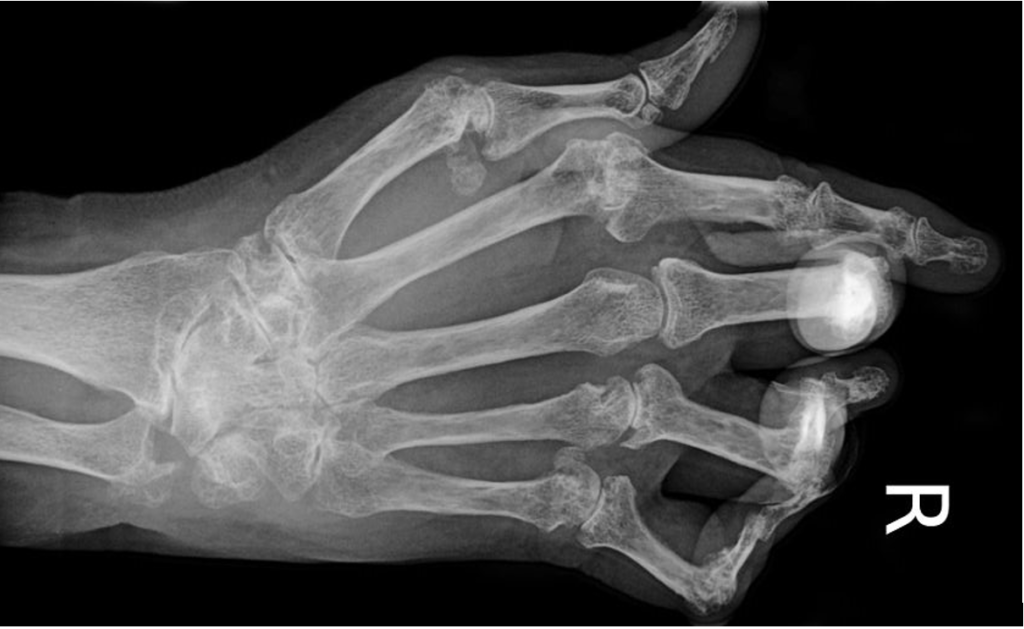

При отсутствии врачебного вмешательства кристаллы мочевой кислоты откладываются в ахилловом сухожилии, фалангах пальцев рук. Учащение приступов артрита приводит к образованию специфических подагрических узелков в виде шишек на суставах, необратимым изменениям сочленений, выражающимся в их видимой деформации. Объем движений существенно снижается, больной постепенно утрачивает профессиональные навыки и способность обслуживать себя в быту.

Рентгенологическое исследование наиболее информативно при рецидивирующем полиартрите. На полученных изображениях в эпифизарных областях обнаруживаются светлые фрагменты. При подагре высокой степени тяжести визуализируются участки костных эпифизов с деструктивными изменениями и отложенными солями — уратами.